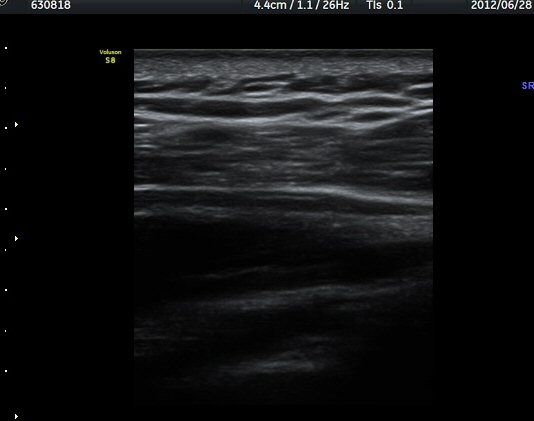

ÁÖ»ç¹Ù´Ã ÈíÀÎ(µ¿¿µ»ó Âü°í) 4ÀÏ ÈÄ °üÂûÇÑ ¼Ò°ß¿¡¼­´Â ³¶Á¾ÀÇ Å©±â °¨¼Ò°¡ ¶Ñ·ÈÇÏÁö ¾Ê´Ù(±×¸² 5, 6).

ÈíÀÎ 14ÀÏ ÈÄ ÃÊÀ½ÆÄ°Ë»ç¿¡¼­ ¾à°£ÀÇ ³¶Á¾ Å©±â °¨¼Ò°¡ °üÂûµÈ´Ù(±×¸² 7, 8)